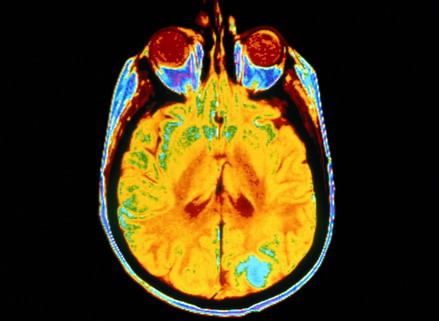

Физиология холотропного дыхания

О том, что гипокапния оказывает церебральный сосудосуживающий эффект, известно давно. Так, Вольф и Леннокс, изучая реакцию мозговых сосудов у животных при изменении содержания О2 и СО2 в крови, установили, что сосуды мягкой мозговой оболочки суживаются при гипокапнии. Дэвис, Вэллэс и многие другие их последователи полагают, что возникновение тета и дельта - активности при гипервентиляции обусловлено развитием гипоксического состояния вследствие снижения кровотока через церебральные сосуды в результате их спазма. Последнее приводит к недостаточному снабжению мозга кислородом и глюкозой, от которых зависит его метаболизм.

По существующим воззрениям, эффект гипервентиляции связан с церебральной гипоксией, развивающейся вследствие рефлекторного спазма артериол и уменьшения мозгового кровотока (Яруллин Х.Х., 1967).

Экспериментальные данные показывают, что гипоксия приводит к деполяризации мембраны нейронов, повышению их возбудимости и общему деполяризационному сдвигу в коре, с чем и связано провоцирование медленноволновой активности (Окуджава В.М., 1969).

Гипокапни́я (от греч. hypó — под, внизу и kapnos — дым) — состояние, вызванное недостаточностью СО2 в крови. Содержание углекислого газа в крови поддерживается дыхательными процессами на определённом уровне, отклонение от которого приводит к нарушению биохимического баланса в тканях. Проявляется гипокапния в лучшем случае в виде головокружения, а в худшем — заканчивается потерей сознания.

При гипервентиляционной гипокапнии повышается возбудимость коры головного мозга. Раньше всего гипервентиляция влияет на осязание, затем на ощущение давления, холода, тепла, боли. Часто возникают явления парестезии в конечностях, в области лица, может отмечаться боль в левой половине грудной клетки и в животе.

Возможны эмоциональные и поведенческие расстройства, синкопальные состояния. Возможно развитие эпилептических и эпилептиформных припадков (вторично по отношению к вазоконстрикции сосудов головного мозга).

Характерным симптомом являются судороги и спазмы скелетных мышц, которые возникают при снижении парциального давления СО2 примерно вдвое по отношению к нормальным величинам. Частым симптомом является карпо-педальный спазм.

Значительную роль в возникновении судорог играет ионизированный кальций, а также нарушения баланса магния. Мышечная слабость обусловлена гипофосфатемией. Аналогом судорог может быть тремор. В тяжелых случаях развивается тетанус. (длительно непроходящий спазм или судорога)

![]()  |

Эти галлюцинации рассматриваются как нечто очень важное или даже священное. Что, в общем-то, заслуживает внимания, но только потому, что здесь на самом деле речь идет не о развитии мозга, а о его деградации. Потому что всякая гипервентиляция ведет не просто к сужению мозгового кровотока, но и к гибели нервных клеток.

Снижение CO2 в легких при углубленном дыхании человека сдвигает рН в щелочную сторону ,что изменяет активность ферментов и витаминов - регуляторов обмена веществ, что нарушает нормальное протекание обменных процессов и ведет к гибели клеток. Если CO2 снизится до трех процентов, а рН сдвинется до восьми, организм погибнет.

в дополнение к обсуждениям в темах Кислород, углекислота и сон и Холотропное дыхание и пранаямы в борьбе с депрессией приведу ссылку, присланную ув. участником под ником dimas в теме Йога туммо: физиологическое обоснование: Hyperventilation as a model for acute ischaemic hypoxia of the brain: Effects on cortical auditory evoked potentials ' Гипервентиляция как модель острой ишемической гипоксии мозга: влияния на корковые аудиторно вызванные потенциалы' Цитата: . Controlled hyperventilation (HV) may be used as an experimental procedure to produce transient ischaemic hypoxia of the brain. ' Управляемая гипервентиляция может быть использована как экспериментальная процедура для вызова преходящей ишемической гипоксии мозга. '

Иными словами, уже в 1991 году было известно, что управляемая гипервентиляция (сиречь, голотропное дыхание ) ведет к предынсультному состоянию (ишемия мозга есть прямой путь к гибели нервных клеток). Хорошо известно также провокационное (диагностическое ) значение гипервентиляционной пробы для вызова большого эпилептического припадка у больных с подозрением на эпилепсию. Последующие исследования только подтверждают негативное влияние гипервентиляции на мозговую функцию: В обзоре 1995 года Hyperventilation therapy for severe traumatic brain injury. прямо утверждается, что Цитата: . hyperventilation is no longer recommended as a first-line therapy for intracranial hypertension or as prophylactic therapy following severe TBI. ' . гипервентиляция не может быть больше рекомендована как первичная терапия при повышенном внутричерпном давлении и как профилактическая терапия после некоторых травм мозга. '

В 2007: Hyperventilation following head injury: effect on ischemic burden and cerebral oxidative metabolism. И, наконец, в самом свежем обзоре 2010 года Hypocapnia and the injured brain: more harm than benefit. окончательно утверждается, что вызванная гипервентиляцией гипокапния приносит "больше вреда, чем пользы" (с).